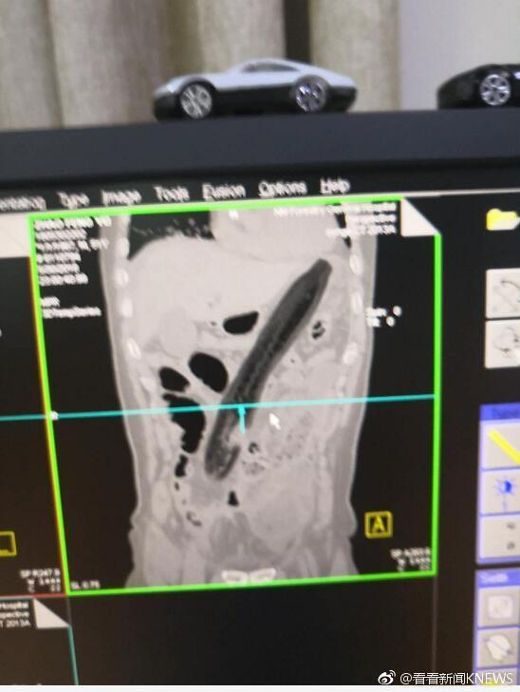

Quả cà tím chiếm toàn bộ khoang bụng của bệnh nhân.

Sau khi chụp X quang, các bác sĩ phát hiện thấy một quả cà tím chiếm toàn bộ khoang bụng, khiến người đàn ông bị viêm màng bụng và viêm túi mật. Không chỉ vậy, các bác sĩ cũng cho biết phổi của ông ta cũng bị ảnh hưởng. Quả cà đã đi từ trực tràng, tới ruột già và đến bụng của người đàn ông.

Quả cà tím dài tới 30 cm.